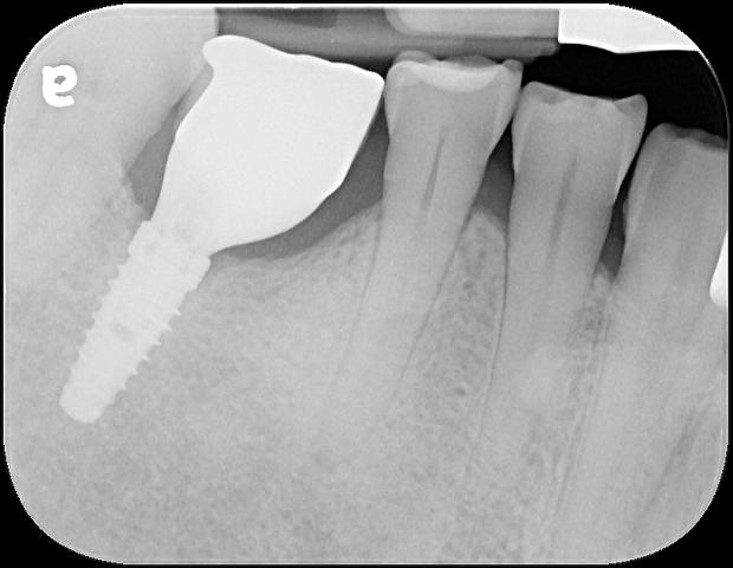

顯微根管治療

製作玻璃纖維釘